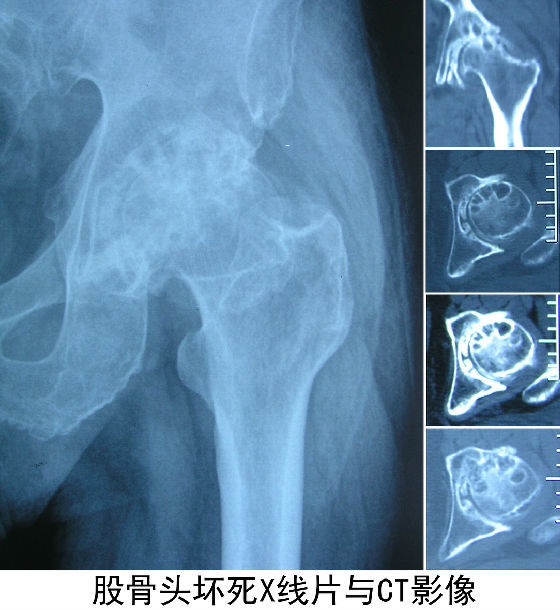

这是一张正常和股骨头坏死,还有横切面的一张图,

当股骨头坏死的话,股骨头的面就会出现凹面和塌陷,这个已经进入阶段性的,分为4个阶段和4个机制。

上边的是股骨头3个期的变化,那我们就简单来说一下啊,首先第一期阶段性破碎性片可以被移除,坏死的骨小梁以后会被新生的骨所吸取,早期的话在片子上是看不清的,那么第二期阶段性在镜头下就会显示出来,里面就会出现塌陷,这时候就会产生疼痛,第三期的时候可以通过技术手段可以修复,但是 从医学角度上来说,股骨头坏死的修复几率很低,到了3期病情会恶化,股骨头的面会越来越塌陷,到了第四期周围的韧带也将会出现问题,髋关节也会受限。神经末梢的感应也会极其敏感,放射疼痛弧,这种疼痛是很难受的。